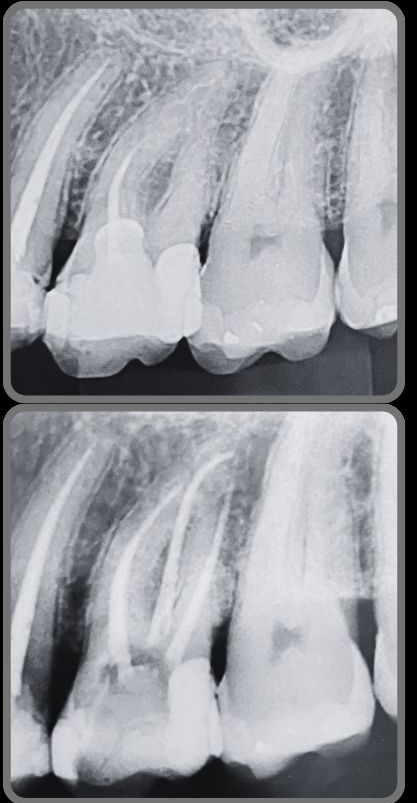

Veja alguns casos de sucesso